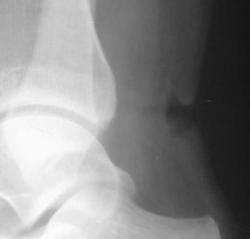

Пропилил богаркой ахиллово сухожилие

ИзображениеИзображение